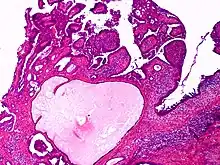

| Apocrine gland carcinoma | |

| Apocrine gland carcinoma, papillary type | |

Apocrine gland carcinoma is a cutaneous condition characterized by skin lesions which form in the axilla or anogenital regions.[1]: 670